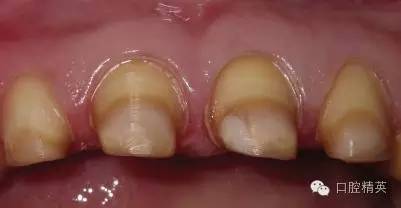

關(guān)于基礎(chǔ)治療。牙周治療和根管治療是美觀修復(fù)的基礎(chǔ)。根據(jù)術(shù)前檢查,常規(guī)先行全口潔治,必要時局部深層次的牙周治療,待牙周情況穩(wěn)定后,再考慮牙體預(yù)備與取模(見圖1、2)。在牙周炎未控制或牙齦紅腫的情況下,是不可能預(yù)備好牙齒,不可能取得清晰的印模,更談不上成功的美觀修復(fù)。

LAVA 全瓷冠強度高,顏色自然,邊緣高度密合,切端可見半透明感,整體效果理想,與修復(fù)前(見圖1)相比取得了醫(yī)患均滿意的效果。